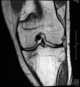

Osteomalacia with fractures

Osteomalacia is a disease characterized by the softening of the bones caused by impaired bone metabolism primarily due to inadequate levels of available phosphate, calcium, and vitamin D, or because of resorption of calcium. The impairment of bone metabolism causes inadequate bone mineralization. [Source: Wikipedia ]